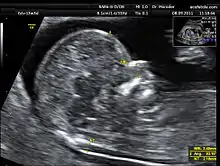

La clarté nucale, petite zone anéchogène (ne renvoyant pas d'écho en échographie) située sur le crâne d'un fœtus humain pendant le premier trimestre de grossesse, permet de dépister certaines anomalies congénitales, en particulier la trisomie 21.

La clarté nucale, comme son nom l’indique, se situe au niveau de la nuque du fœtus. Elle est due à un petit décollement entre la peau et le rachis et correspond à une zone dite anéchogène (c’est-à-dire qui ne renvoie pas d’écho lors de l’examen). Tous les fœtus présentent une clarté nucale au cours du premier trimestre, mais cette clarté disparaît ensuite.

La mesure de la clarté nucale[3] doit avoir lieu au cours de la première échographie de la grossesse, c’est-à-dire entre la 11e semaine et 13 semaine + 6 jours d’aménorrhée. Il est impératif que l’examen soit fait à cette période, car passé trois mois, la clarté nucale disparaît.